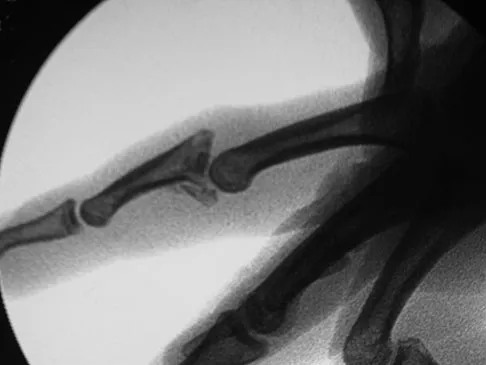

A 19-year-old collegiate baseball player injures the ring finger on his dominant hand while sliding headfirst into second base. He reports that he is unable to actively flex or extend the distal interphalangeal joint of the finger. Radiographs are shown in Figures 19a and 19b. What is the anatomic lesion leading to this injury?